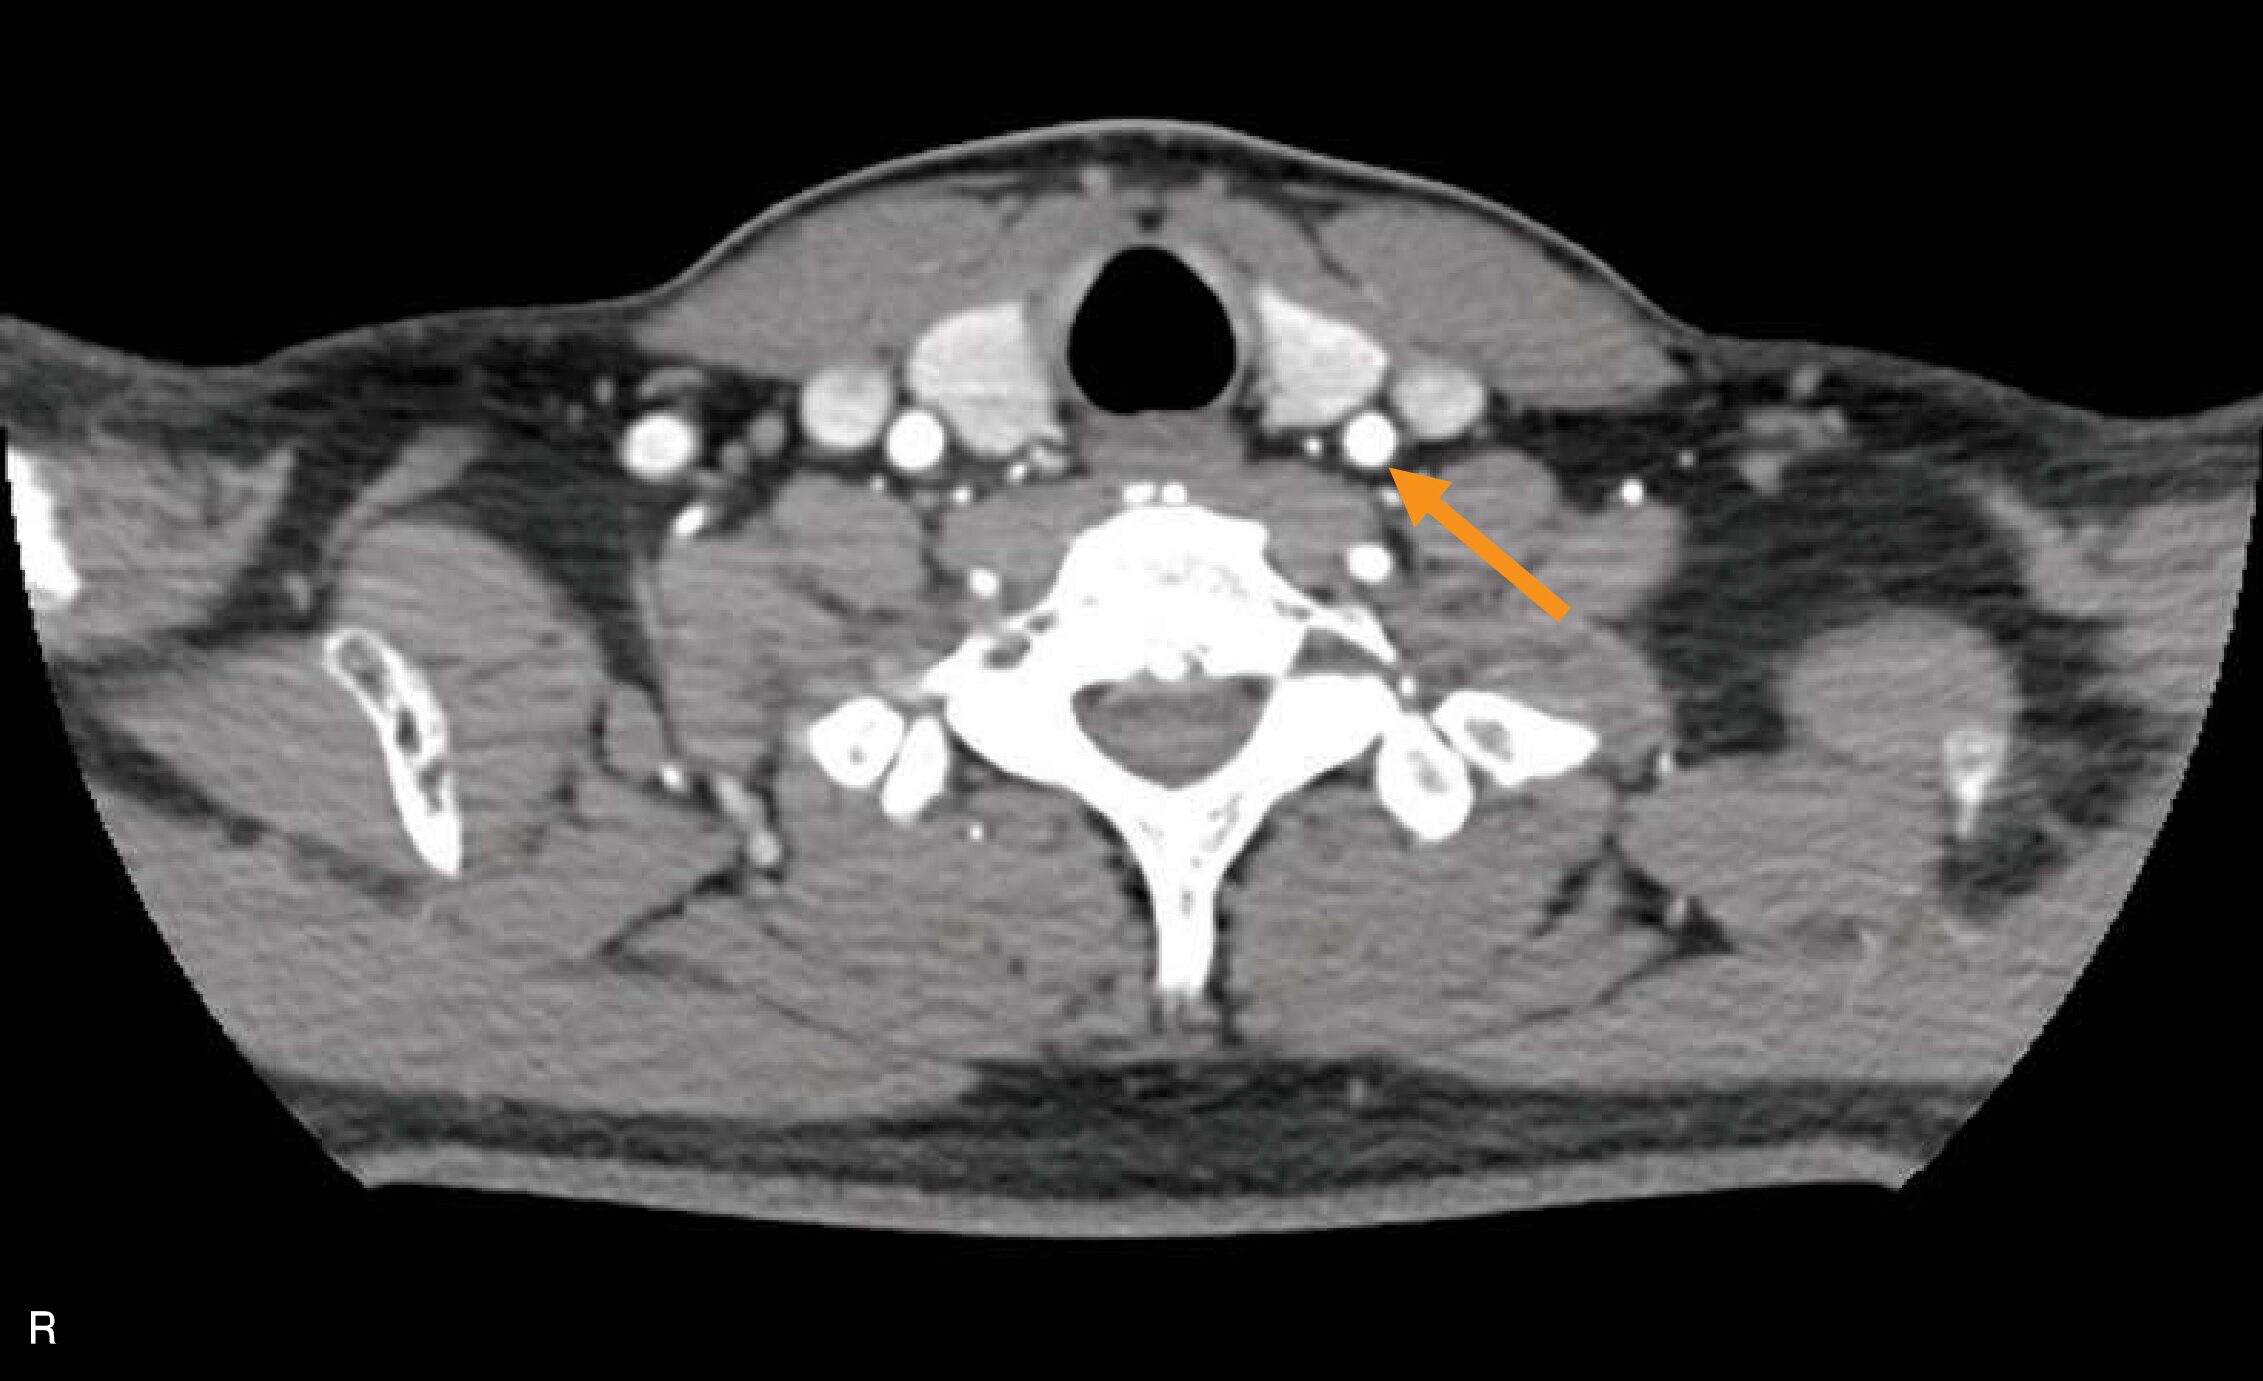

頸部の造影CT像(別冊No.11)を別に示す。矢印で示すのはどれか。

Q93 / 20画像工学